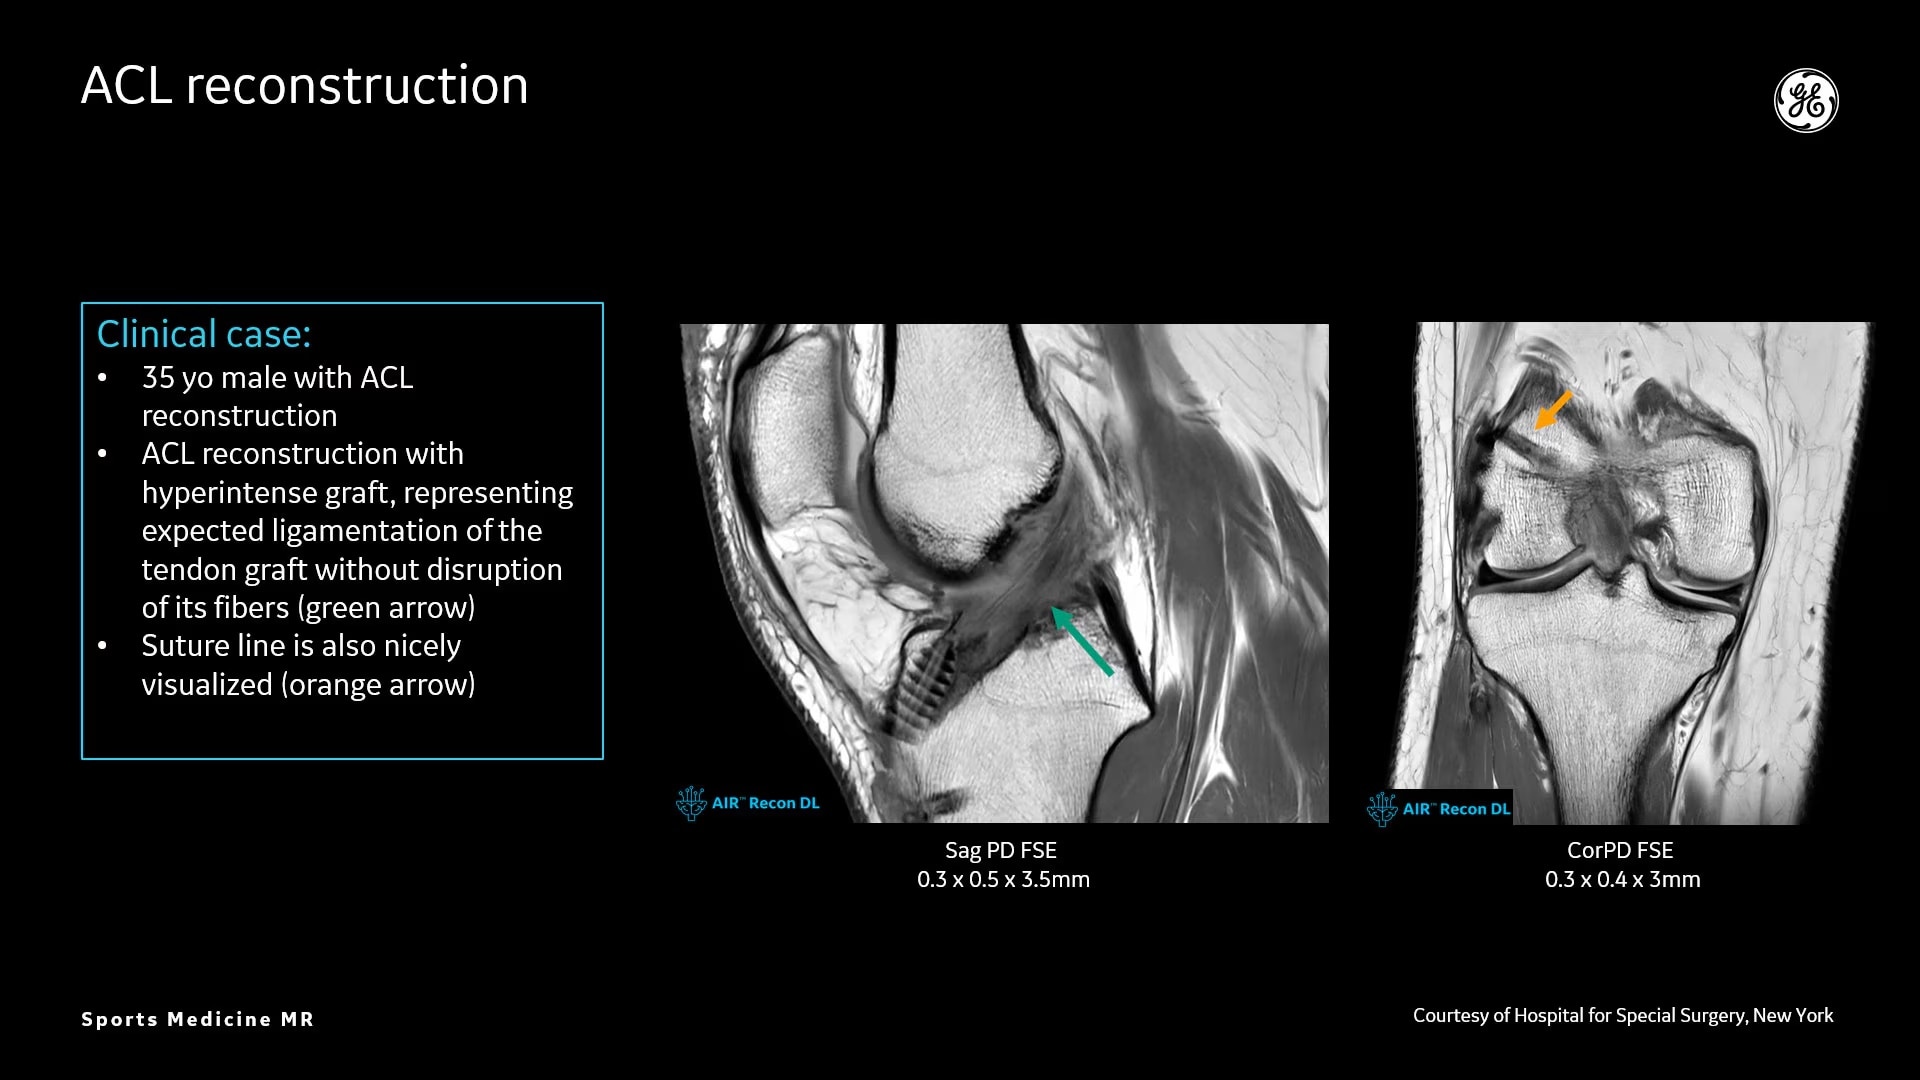

AIR Recon DL provides high-resolution images with increased SNR at markedly reduced scan times. This technology optimizes the depiction of even small injuries, such as meniscal, labral and ligament tears. The reduction in scan times increases flexibility for individually tailored MR protocols with an additional oZTEo sequence for detailed fracture assessment.

Delivering a comprehensive knee assessment in athletes

Clínica CEMTRO’s study of a complex knee injury and the use of oZTEo and AIR Recon DL.